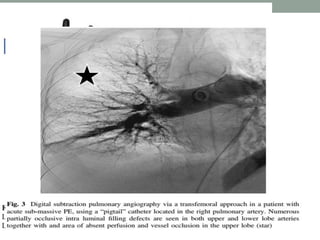

7) Perform selective

conventional angiography

by administering 10 ml of

contrast at 5 ml/s preferably

in the 20° left anterior

oblique (LAO) view to

visualise the left pulmonary

artery and preferably the

20° right anterior oblique

(RAO) view to visualise the

right pulmonary artery. The

RAO cranial view may also

be useful.